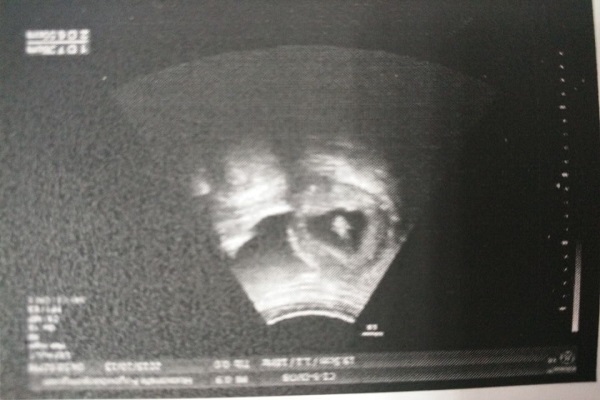

阴式B超真的有那么可怕吗?可能是你误解了,今天就来带大家了解一下两种B超的特点和区别。

精准、直观,能看到子宫和附件疾病

能提前发现早早孕

对比之后可以发现,二者检查的方式不同,准确率也不同,相比之下前者更具优势,如果是宫外孕、瘢痕妊娠这种特殊情况,是不可能有时间憋尿的,普通B超太慢了,为了保障母婴安全,快速做出诊断,还是做阴超比较合适。

探头进入体内一般在4厘米左右,触及不到宫腔,离胎儿还有一定距离,所以孕妇也能做,而且它也没有辐射,不用担心致畸,非常安全。有的人做完检查发现*裤内**有血迹,怀疑是检查导致的,其实不能这么说,因为有的女性体质弱,胚胎发育不好,本来就有一定危险性,做阴超反而能帮助你尽早发现胚胎异常状况。